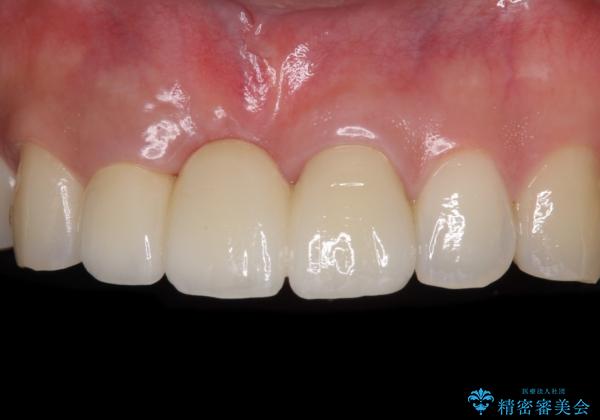

歯肉移植により歯肉ラインや歯の形態を整えることができ、ブリッジによる補綴としたことで舞えば全体の色調を整えることができました。